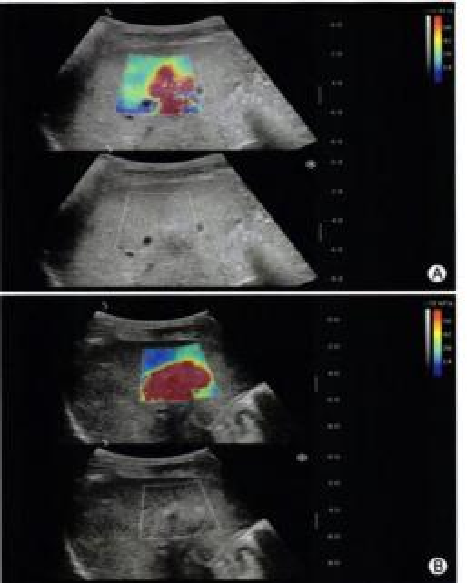

实时剪切波弹性成像

评估组织的软硬,并且提供定量数值,从而提示组织的良恶性。

鉴别诊断、精准分级、定量评价、穿刺引导、疗效评估、随访观察

image.png

恶性占位常常向周边组织进行侵润及扩散,二维很难观察到浸润部分的边界。使用实时剪切波成像能够对占位及周边组织进行硬度评估,通过颜色编码来区分不同组织的硬度信息,直观的观察占位组织的边界信息,更方便区分占位组织和正常组织的边界,准确评估消融范围。